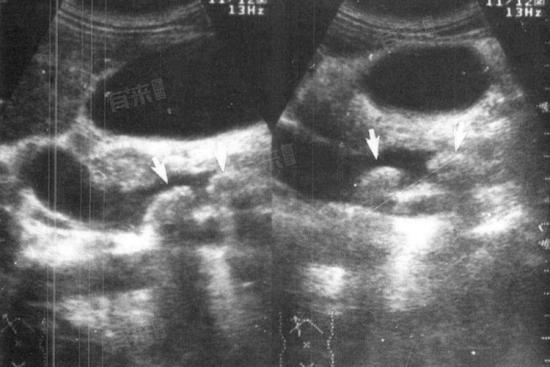

- 当组织发生病变或存在一些异常情况时,就可能导致回声不均匀。当组织出现炎症时,炎症部位会有充血、水肿,细胞的形态和结构发生改变,组织的密度也会有所不同,这就会使超声波在传播过程中遇到不同的声学界面,反射回来的声波信号强弱不一,从而在超声图像上表现为回声欠均匀。

- 此外,组织中出现肿瘤时,肿瘤细胞的生长方式、排列以及肿瘤内部的血供情况等与正常组织有很大差异,肿瘤组织的声学特性也不同于周围正常组织,超声波在肿瘤组织和正常组织之间传播时,会产生不同程度反射、折射和散射,导致回声不均匀。另外,组织的纤维化、钙化等病变也会影响超声波传播和反射,造成回声欠均匀的表现。

所以回声欠均匀是超声检查中提示组织或器官可能存在病变或异常的重要线索,但仅凭这一表现不能明确诊断具体疾病,还需要结合患者的临床症状、体征以及其他检查结果进行综合分析,以明确病因并制定相应的治疗方案。